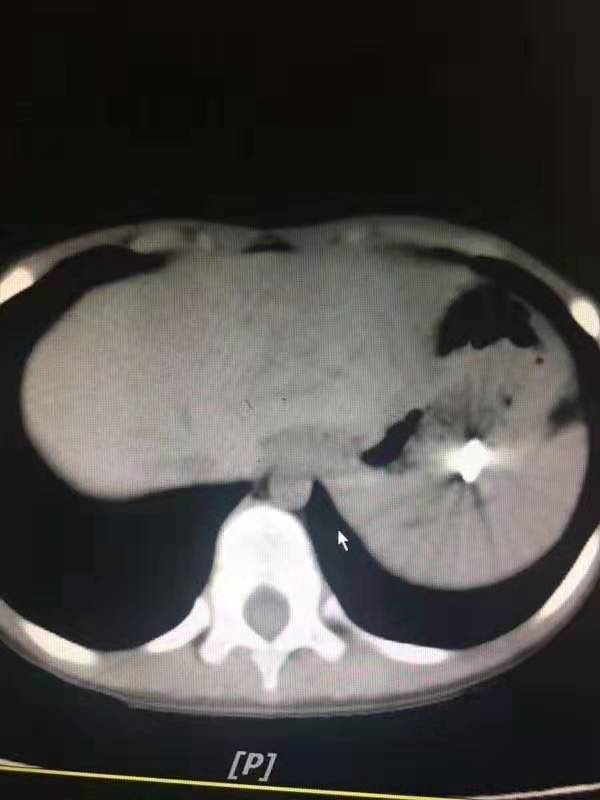

是采取胃镜探查还是腹腔镜探查?刘超医生带着刚刚办好住院手续的孩子做了x线片和CT,还好,钢钉还在孩子的胃里,胃壁没有穿孔。

19:40,孩子被推进了手术室,可胃镜下的一幕又让医生们吃了一惊,明明CT上显示钢钉在胃里,可是胃镜下的胃里空无一物。

医生们继续向下寻找,终于在十二指肠球部和降部交界的地方发现了卡住的钢钉。钢钉的尖端已经刺入了十二指肠球部的粘膜,这后面就是重要的大血管,一旦钢钉刺穿肠壁和血管后果不堪假想。